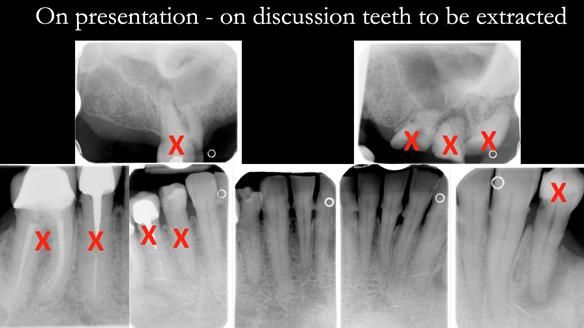

- The upper natural teeth have hopeless prognosis due to dental caries.

- The LR6, 5, 4 have guarded prognosis because of dental caries.

- The lower front teeth (LR3 – LL3) have better prognosis (although, I think there is high chance of loss – over the next 10 - 15 years). However, I do not believe it is right to remove them as they are in good condition compared with the other teeth and coping with a lower full denture is far more difficult (affecting your quality of life) than a lower metal based partial denture supported by natural teeth as proposed in the treatment plan below.

- The forces placed on the teeth are large (bruxism). This will make the dentures proposed in the treatment plan below wear, chip and break more quickly. Therefore, the final dentures will require metal reinforcement to make them as robust as possible.